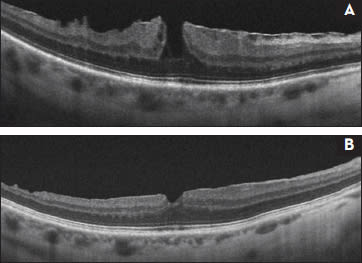

OCT can reveal unusually “thick” membranes in some lamellar holes that represent residual hyaloid on the inner retinal surface after apparent PVD (Figure 3). In addition, it is evident that lamellar macular holes can progress both anatomically and visually and can be the cause of significant visual dysfunction in some eyes.

Figure 3. A lamellar macular hole associated with “thick” epiretinal membrane due to residual hyaloid on the inner retinal surface (white arrows). This eye had a previous retinal detachment. Visual acuity was 20/80.

Several recent clinical studies suggest both anatomic and visual success can be achieved in symptomatic eyes with lamellar macular hole using vitrectomy with membrane peeling techniques (Figure 4).3-6 Such successes can be achieved with an acceptable complication rate.

Figure 4. A 53-year-old man with progressively decreasing vision to 20/60 in the right eye associated with ERM and lamellar hole (A). One year after PPV with ERM peel assisted with intraoperative triamcinolone (B). Despite mild persistent retinal thickening, the visual acuity was 20/25.